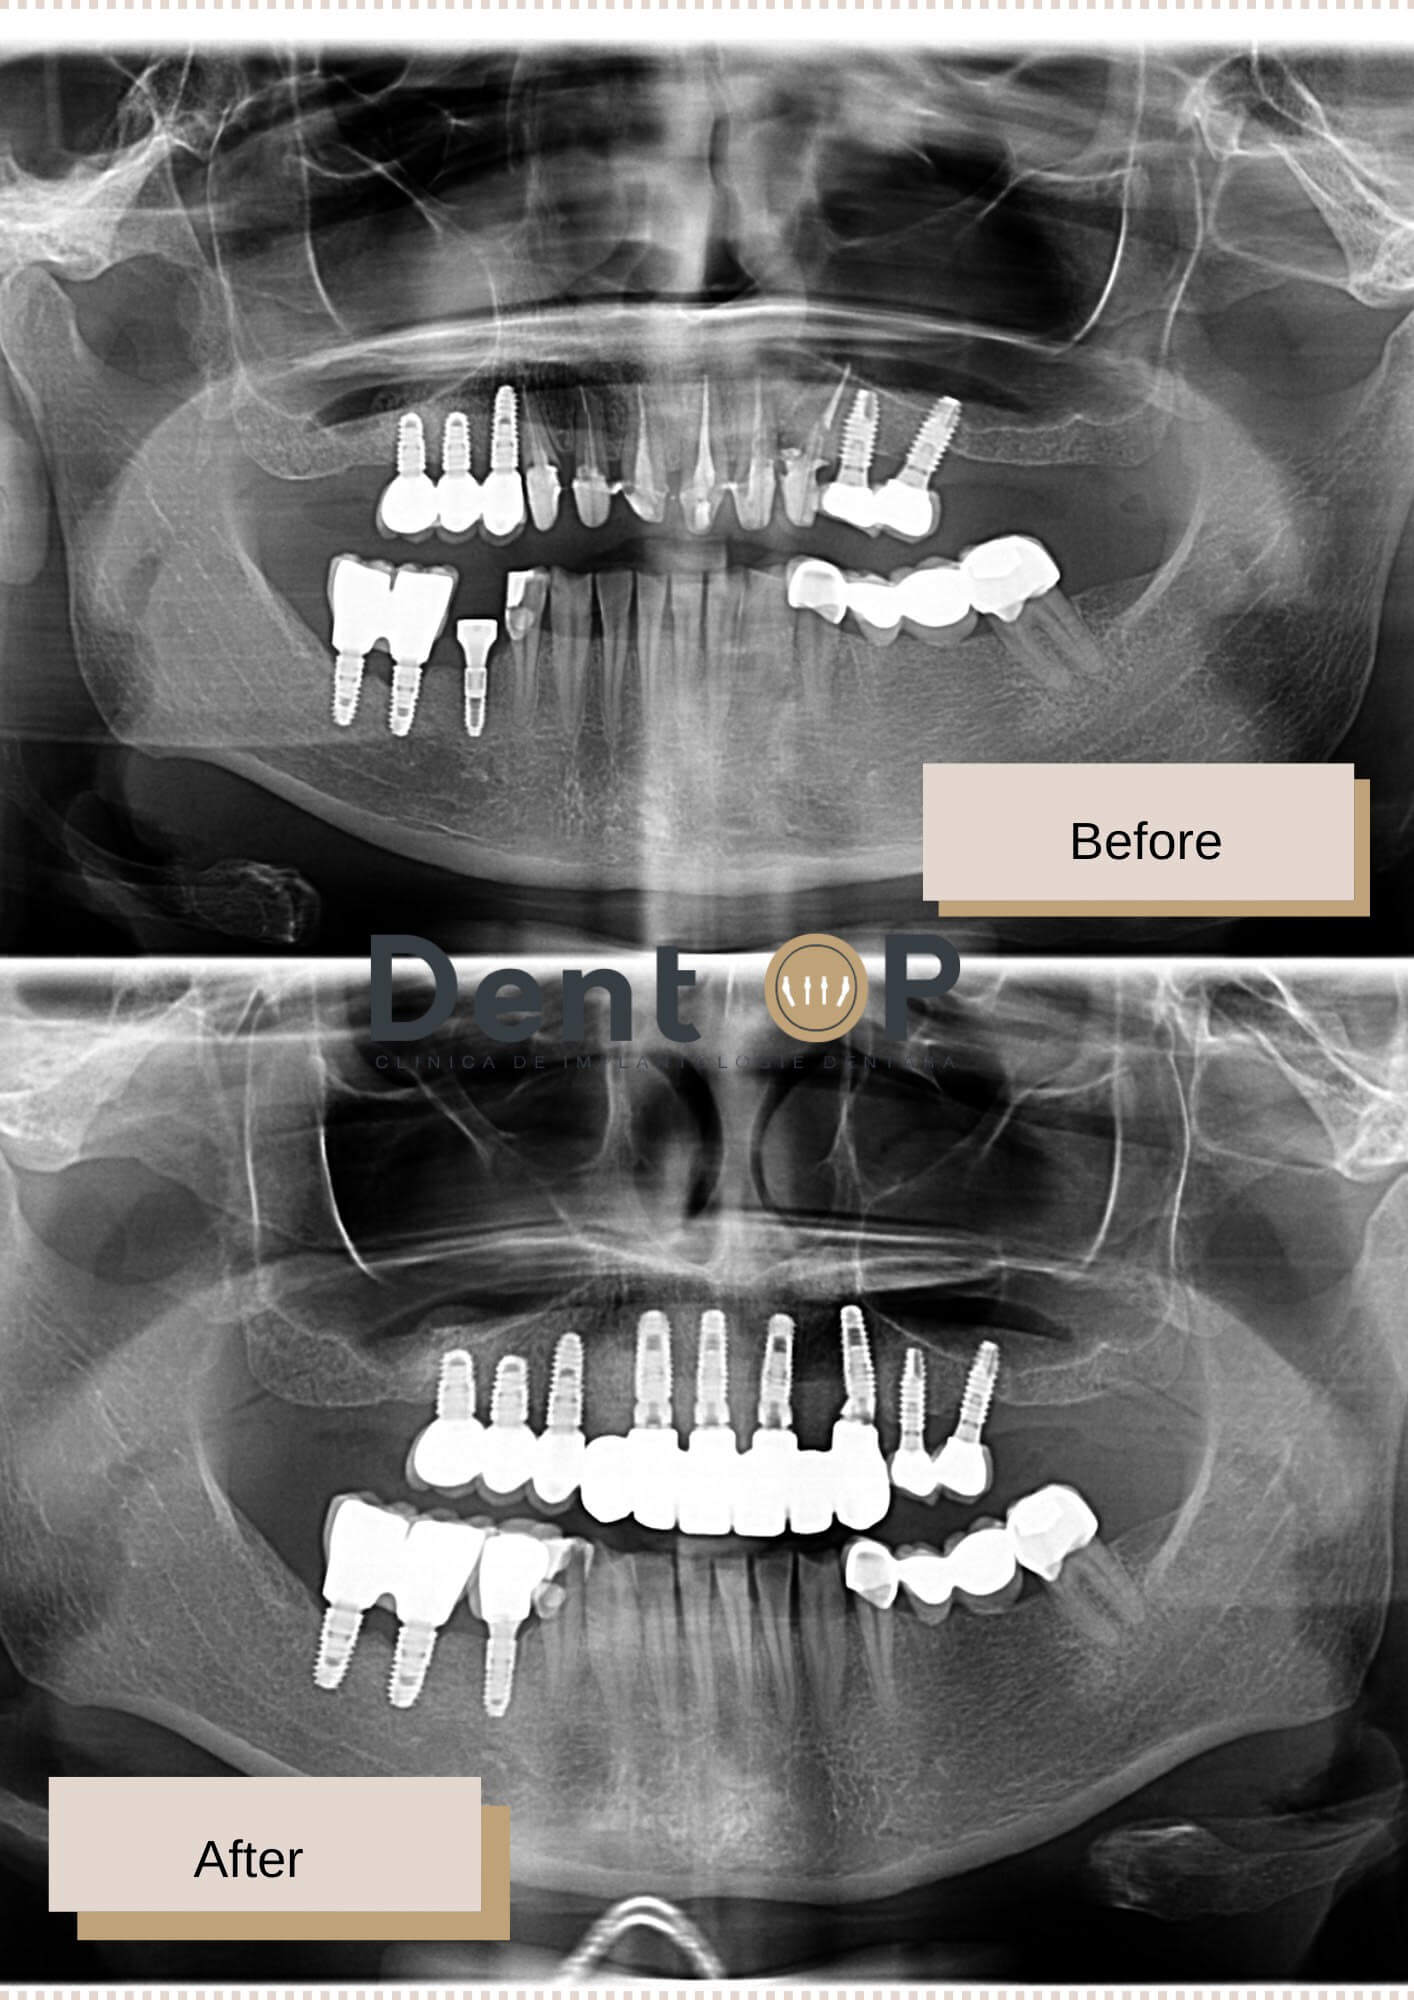

În cadrul radiografiilor de mai jos putem observa dantura pacientei înainte și după inserarea celor 4 implanturi dentare la maxilar.

I-au fost inserate în cadrul intervenției 4 implanturi dentare la maxilar, iar pacienta nu a simțit nicio durere datorită Sedării Conștiente, procedură medicală efectuată de către Medicul ATI. În doar 24h, pacienta a primit și lucrarea provicorie pe care a purtat-o timp de 4-6 luni. În toată această perioadă, pacientul a avut o dietă semi-lichidă, moale pentru a putea ajuta vindecarea implanturilor și tratamentelor efectuate.